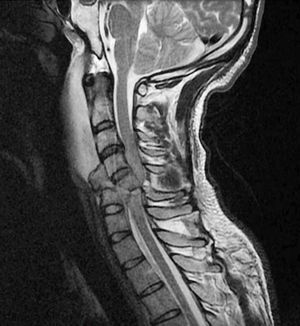

This is a severe trauma caused by a car accident, characterized by Hyper flexion tear-drop fracture-dislocation of C5 vertebra, (severe axial loading with neck flexed) with small tear drop fracture anteriorly and large part against the cord and fractured left lamina of L5 as well as marked posterior displacement of the fractured C5 vertebra with significant cord compression and intrasubstance haemorrhage. A spinal cord injury (SCI) is damage to the spinal cord that causes changes in its function, either temporary or permanent. These changes translate into loss of muscle function, sensation, or autonomic function in parts of the body served by the spinal cord below the level of the lesion. Injuries can occur at any level of the spinal cord and can be classified as complete injury, a total loss of sensation and muscle function, or incomplete, meaning some nervous signals are able to travel past the injured area of the cord. Depending on the location and severity of damage along the spinal cord, the symptoms can vary widely, from pain or numbness to paralysis to incontinence. đˇâ˘Medicogramâ˘

Looks like this patient is permanently paralyzed now!!Lucky to be alive??

I was wondering what would return after decompression surgery as the cord doesn't actually seem severed.....even the tiniest bit of function would be a blessing